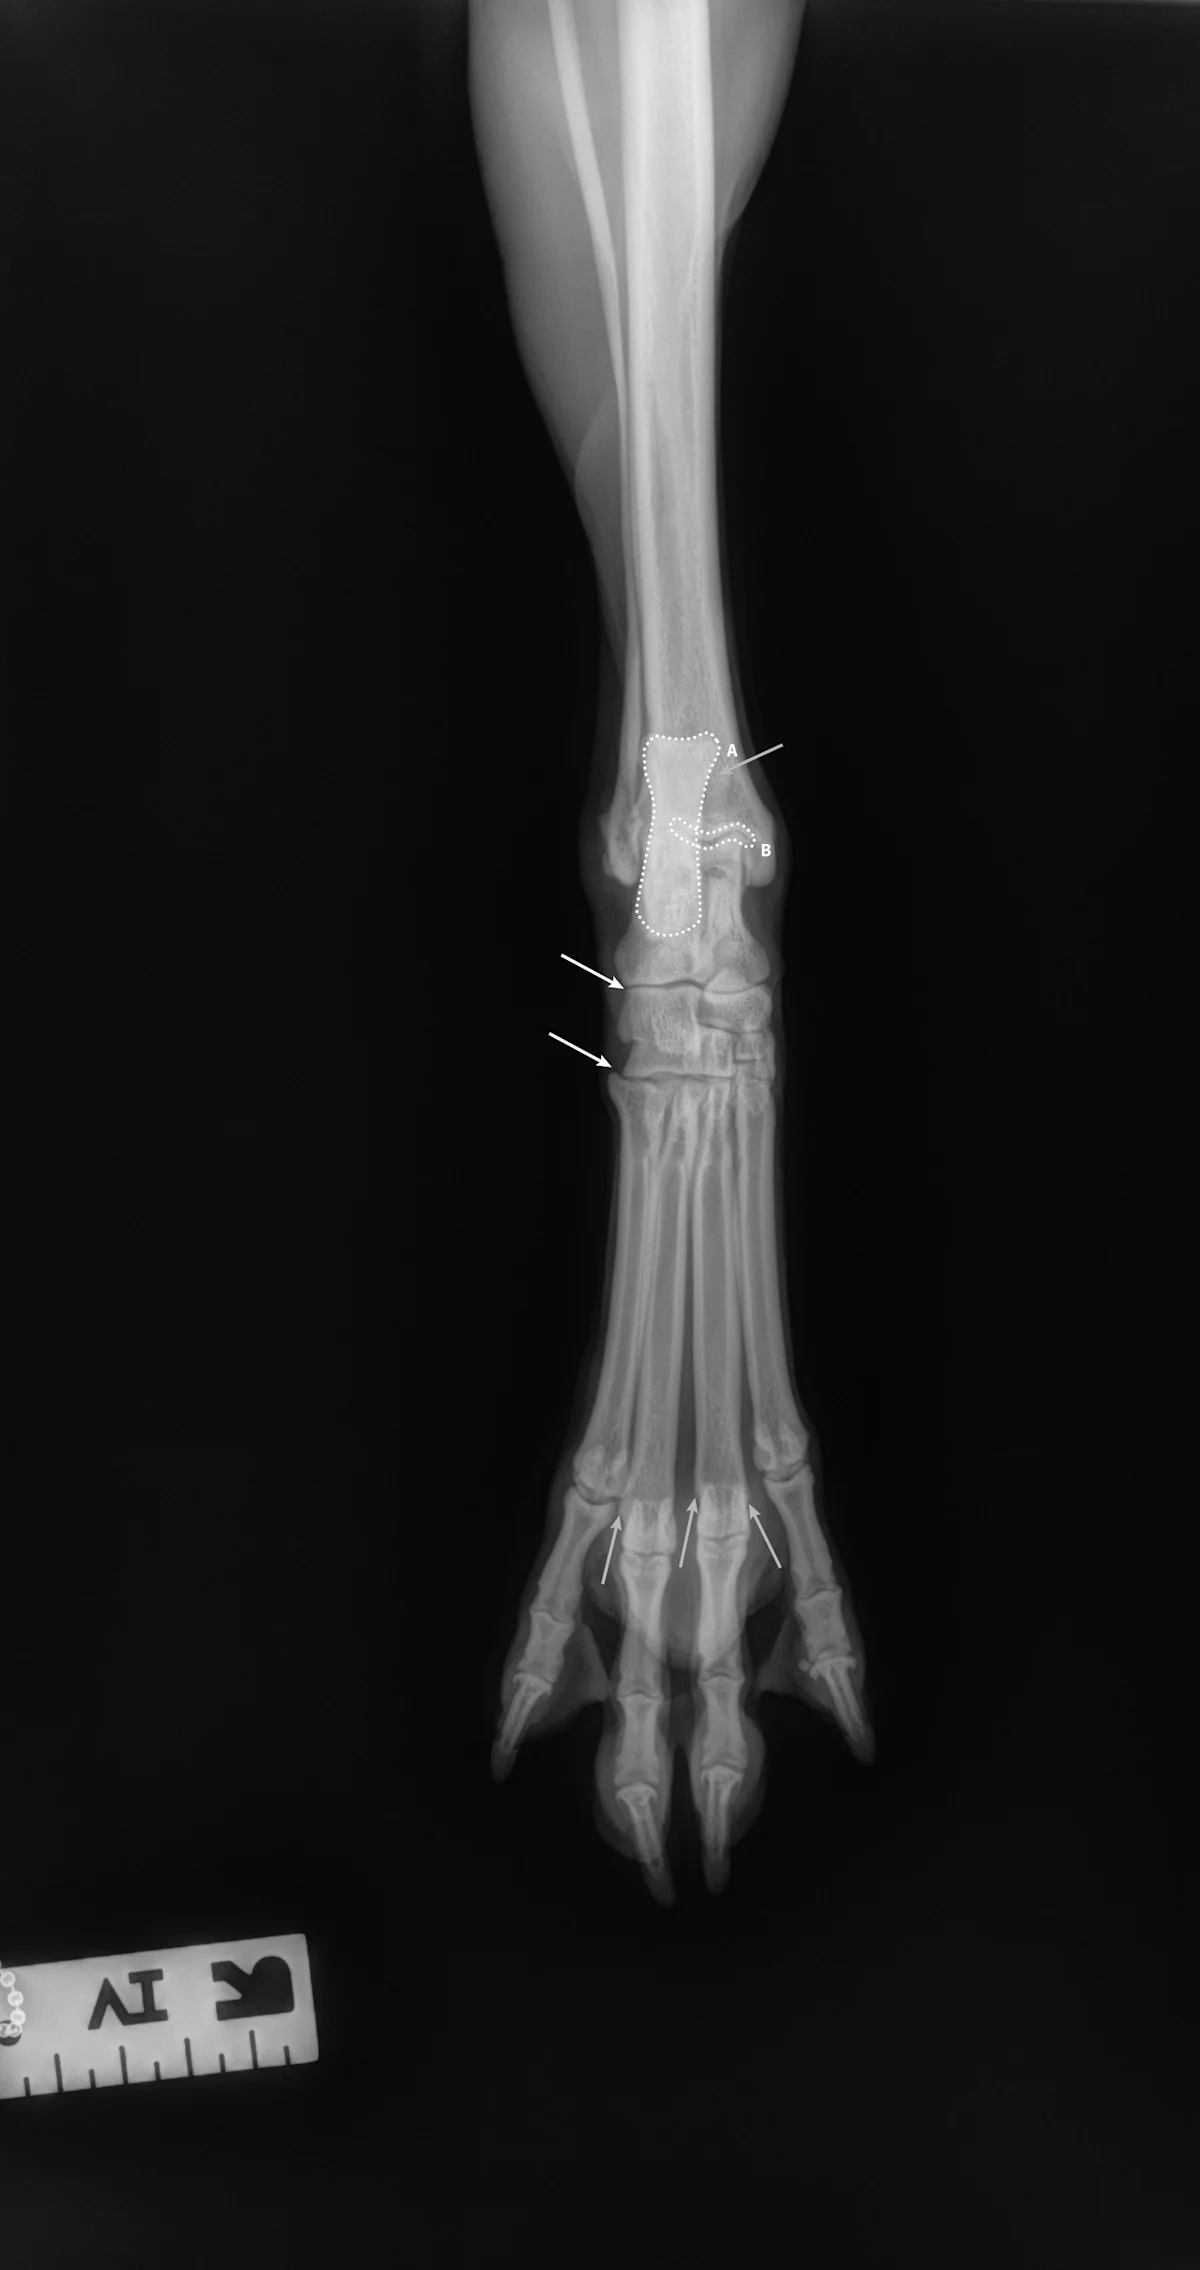

Step-by-Step: Positioning a Pelvic Limb for a Dorsal/Palmar View of the Digits

Step 1: Position the Patient

Place the patient in dorsal recumbency. Center the abdomen over a V-trough sponge positioner to keep the body straight; ensure the pelvis and caudal abdomen are outside of the trough. Make sure both pelvic limbs are completely extended and the unaffected limb is not in the imaging view.

Author Insight

To evaluate the entire bony structures, the digits may need to be separated manually (using either a wooden spoon to press down and spread the digits or using gauze without woven radiopaque detectors) and taped down.

Step 2: Position the Beam

Center the collimator beam over the tarsometatarsal joints to include the distal metatarsals and all digits (the tarsus can also be included).

All digits should be separated and clearly visible. The bony edges of the metacarpal bones should be parallel to each other (arrows), and all phalanges (P1 [A], P2 [B], P3 and nail [C]) should be included.